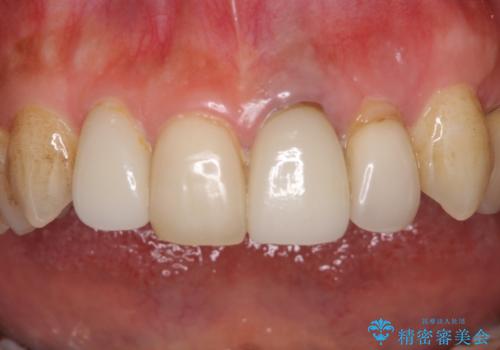

歯肉移植を用いた前歯のオールセラミックブリッジ

- 前歯が折れてしまい、ブリッジによる補綴治療を希望して来院された患者様です。

折れている前歯は抜歯をし、痩せてしまう歯肉は移植術により増大させることで審美面を回復した後、オールセラミックブリッジにて補綴することとしました。

インプラントかブリッジか悩むところでしたが、既に治療されている前歯のクラウン周りの変色が気になっていたため、ブリッジにより色調を合わせたオールセラミックを装着することを選択しました。